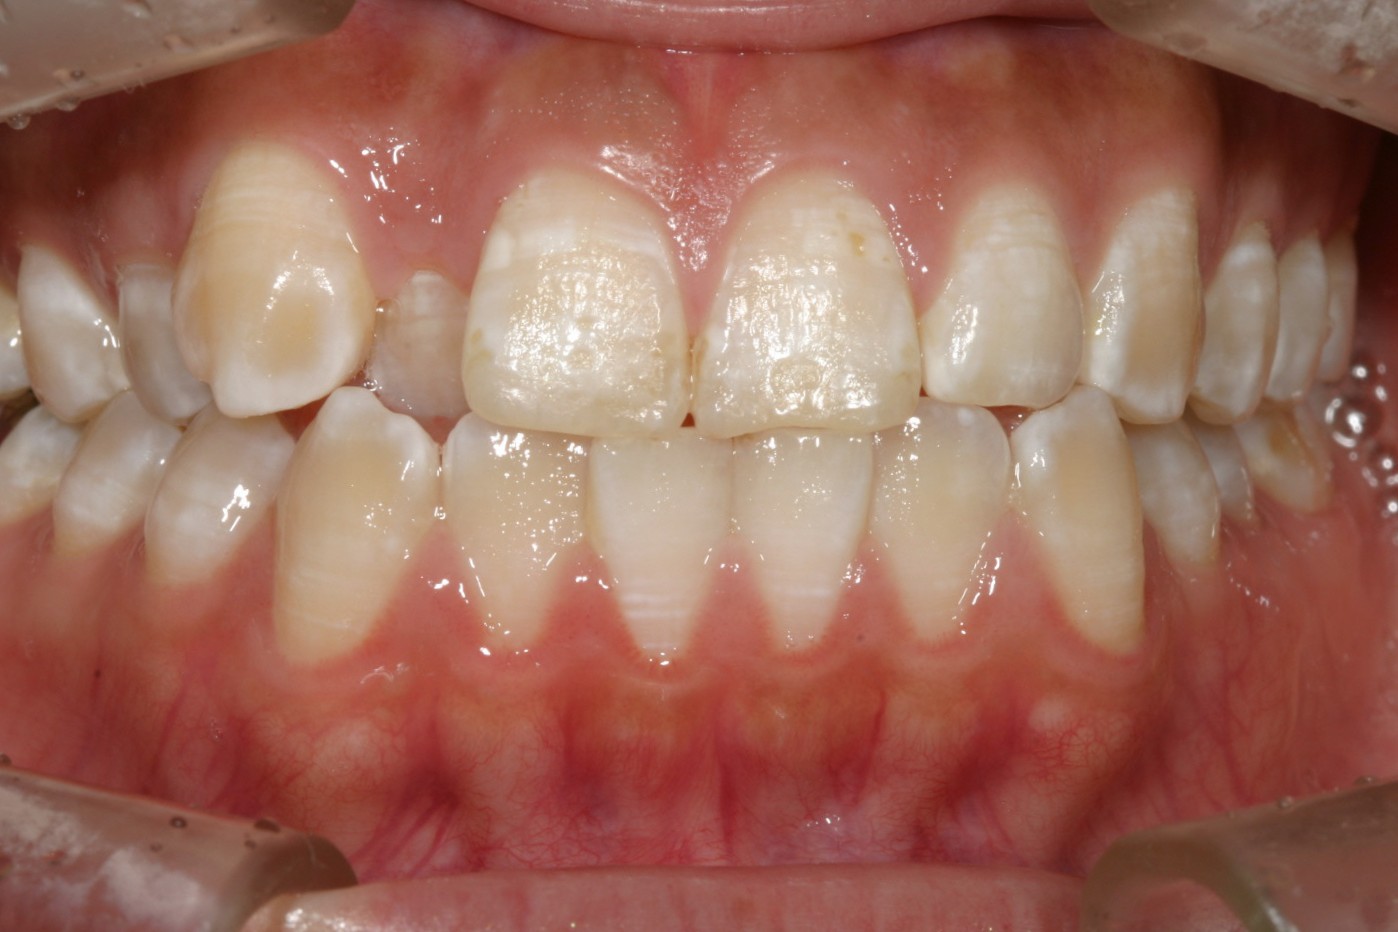

右上の犬歯が飛び出しているのが気になります。

下顎前歯が翼状捻転しています。

オーバージェットが少なく切端咬合になっています。